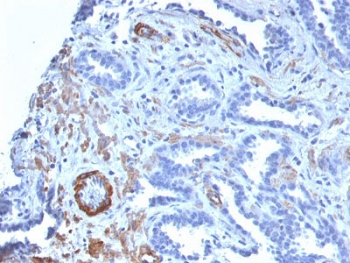

IHC: Formalin-fixed, paraffin-embedded human colon carcinoma stained with SMMHC antibody (MYH11/923).